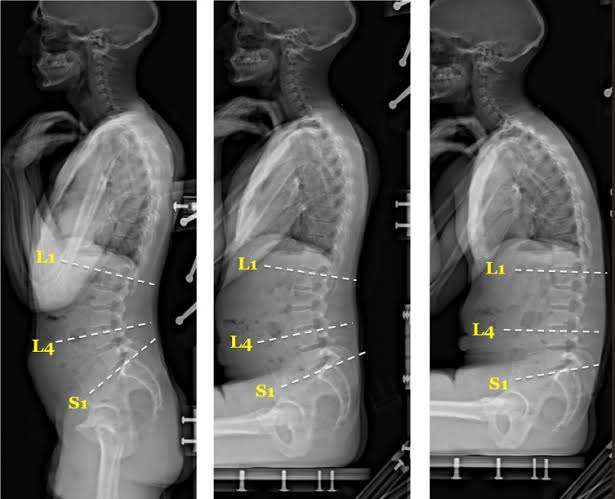

Best Chiropractic sciatica pain relief doctor in chennai tamilnadu for instant relief from sciatica back Pain, L4 L5 S1 disc buldge and degeneration problem and posture correction to solve recurring Pains.